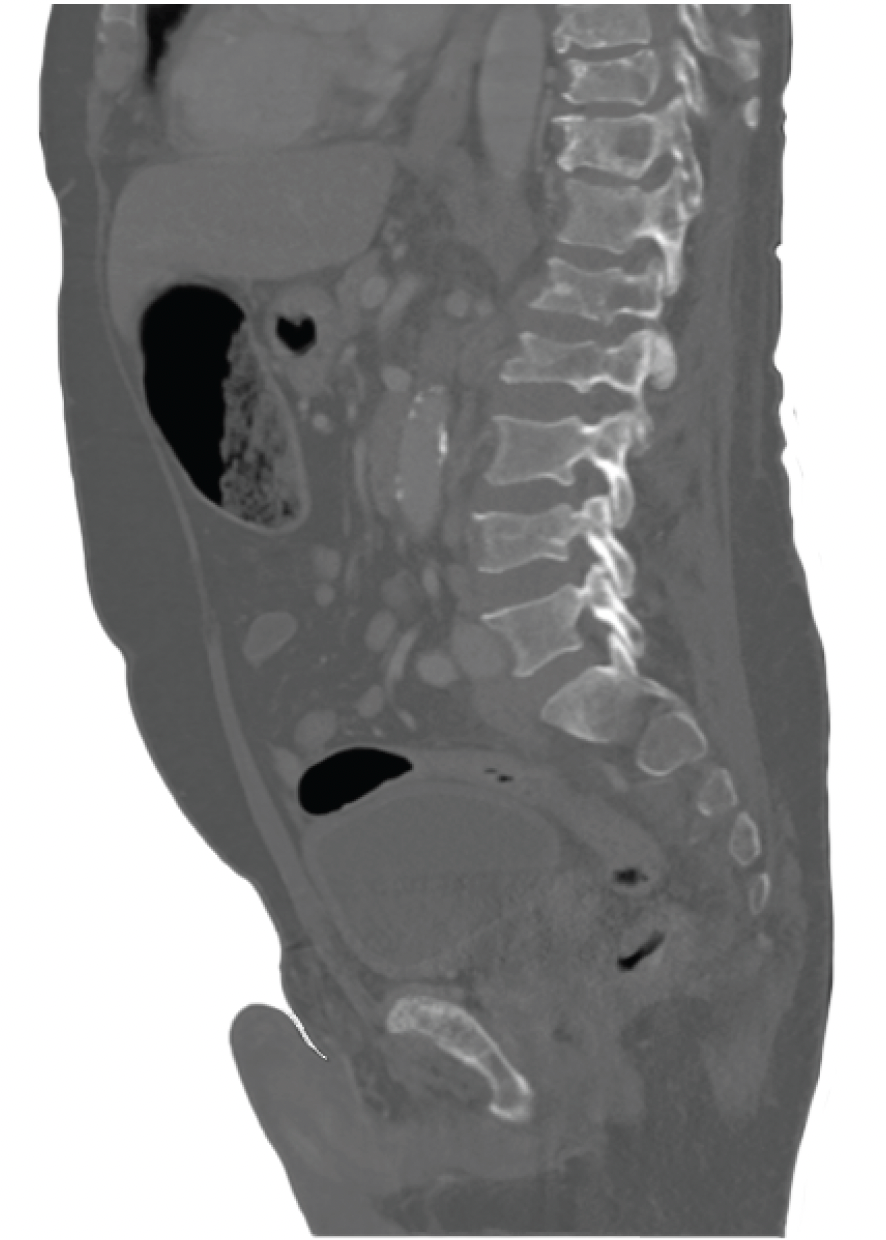

PATIENT CASE.

FIGURE 1.

FIGURE 2.